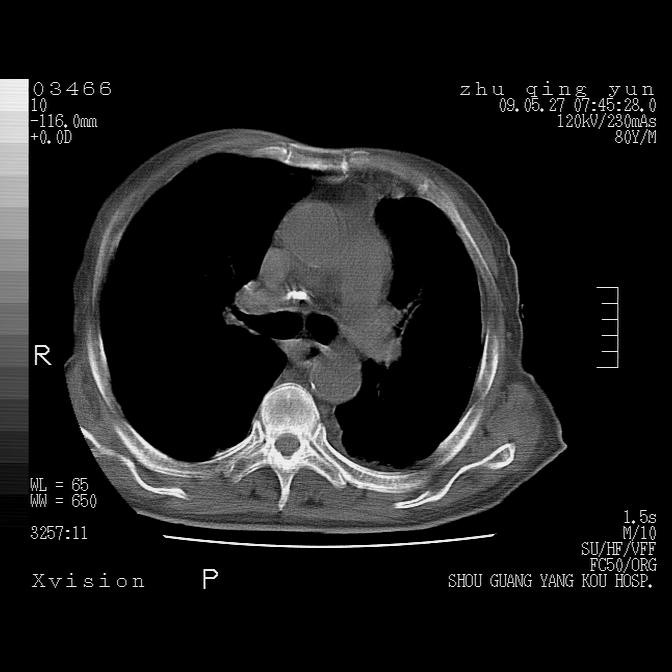

病人男性,年龄80,气喘来院,其他病史不太详细,1月前有过恶心,呕吐,在当地人民医院做过钡餐,诊断胃炎,

1)考虑左肺中央型肺癌并阻塞性肺炎,后下纵隔受侵伴纵隔淋巴结转移。2)双侧少量胸腔积液,胸膜增厚。3)心包积液。

左肺下叶见多发片状及结节状病灶,左肺基底段支气管闭塞,纵隔内见多发淋巴结肿大,纵隔向左侧移位,左侧胸廓变小。应该是左肺下叶中心型肺癌,纵隔淋巴结转移,左侧肺内转移,左肺基底段肺不张,阻塞性肺炎。

1)考虑左肺中央型肺癌并左肺下叶阻塞性肺炎、不张;左胸膜腔积液、心包积液、纵隔淋巴结转移;癌肿累及左心房。2)左心室大。冠状动脉壁钙化斑。